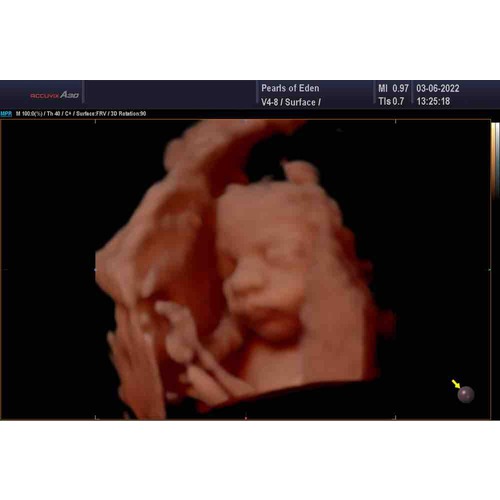

Had ook de placenta aan de voorkant maar een prachtig beeld van ons meisje, dus kan prima 😁😊

Ik had ‘m ook aan de voorkant. En wij hebben met de 3D echo mijn prachtige ...